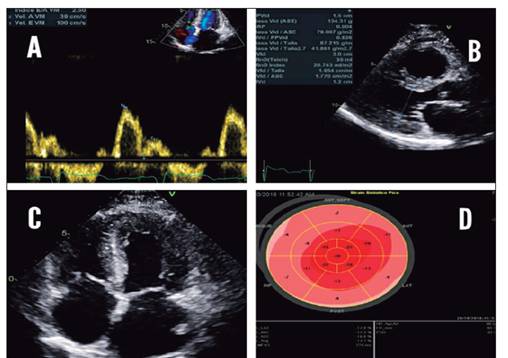

El ecocardiograma transtorácico (figura 2) revela hipertrofia leve del ventrículo izquierdo con remodelado severo concéntrico e hipertrofia moderada del ventrículo derecho, con función contráctil biventricular conservada. El strain 2D longitudinal global se encuentra deprimido en segmentos basales y medios, pero conservado en segmento apicales. Las paredes de ambos ventrículos lucen engrosadas de aspecto infiltrado. El atrio izquierdo luce dilatado moderadamente.

Asocia disfunción diastólica tipo III con patrón restrictivo e insuficiencia tricuspídea severa por movimiento restrictivo de las valvas (patrón III B).